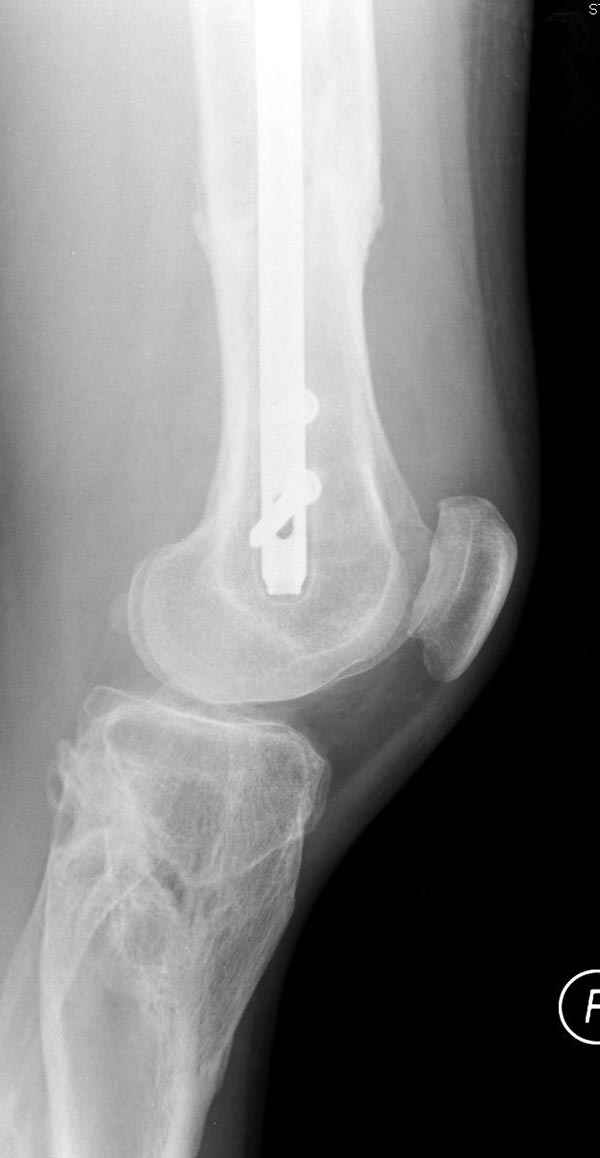

если первые 4 месяца послеоперационного периода проходил без проблем, но на 5 месяце появились боли в дистальном отделе бедра и температура, т.е. симптомы медуллярного инфицирования (рис №3, №4).

Замена реконструктивного штифта “Custom made Nail” с антибиотиком (рис №5, №6),

после промывки канала с рассверливанием внутреннего кортекса, через 4 недели антибиотический штифт удалили, оспалителный процесс остановлен и бедро сросся.